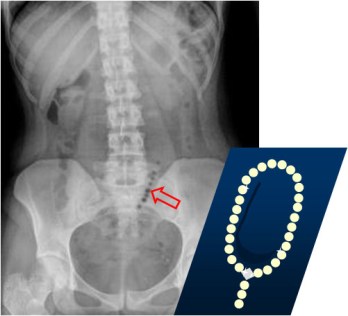

SIGNO DEL COLLAR DE PERLAS o DEL ROSARIO DE CUENTAS

Hilera de burbujas en disposición vertical u oblicua, vista en la radiografía de abdomen en decúbito supino o en bipedestación. Representa pequeñas cantidades de aire atrapado en las válvulas conniventes del intestino delgado, predominantemente lleno de líquido. Se presenta en la obstrucción mecánica del intestino delgado, aunque rara vez también puede verse en el íleo paralítico, gastroenteritis o tras la aplicación de un enema salino.

Este signo también se ha llamado Signo del rosario de cuentas. Aquí vemos un ejemplo en un cuadro obstructivo de delgado: